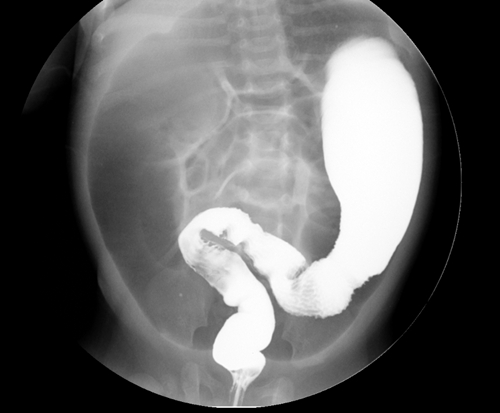

專家們經(jīng)過(guò)討論,結(jié)合消化道造影檢查結(jié)果,判斷麗麗患有先天性巨結(jié)腸,立刻將其轉(zhuǎn)入新生兒外科進(jìn)行治療。

先天性巨結(jié)腸是新生兒最常見(jiàn)的腸神經(jīng)系統(tǒng)(ENS)發(fā)育障礙性疾病,是小兒便秘最常見(jiàn)的先天性消化道畸形,多見(jiàn)于乙狀結(jié)腸、直腸。受累腸管發(fā)生痙攣狹窄,無(wú)法像正常腸道一樣蠕動(dòng),腸內(nèi)容物沒(méi)有辦法正常排出,堆積在腸道內(nèi),導(dǎo)致病變近端的腸管嚴(yán)重?cái)U(kuò)張,逐漸形成巨結(jié)腸改變。